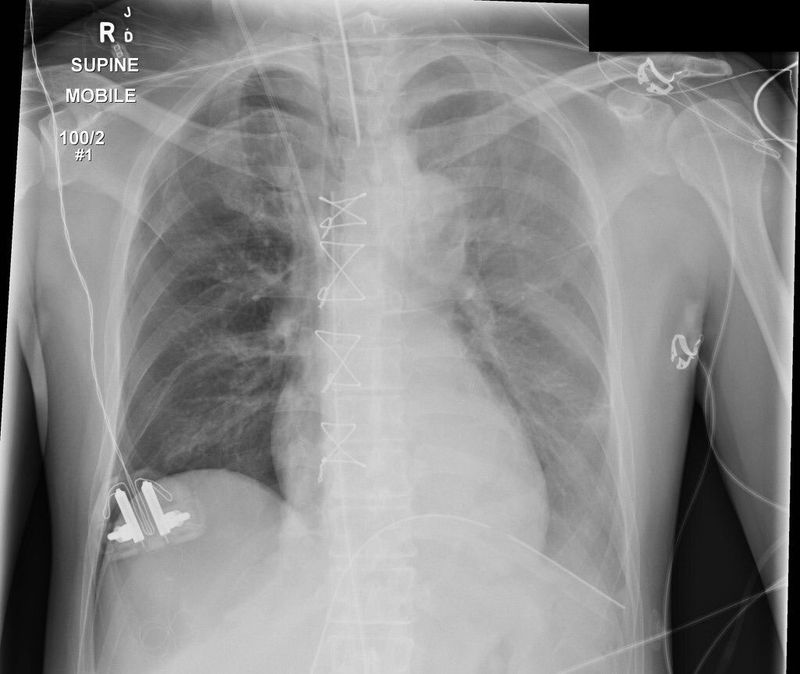

Post CABG chest x -ray

What is the finding and dx

Pneumothorax

Cabg